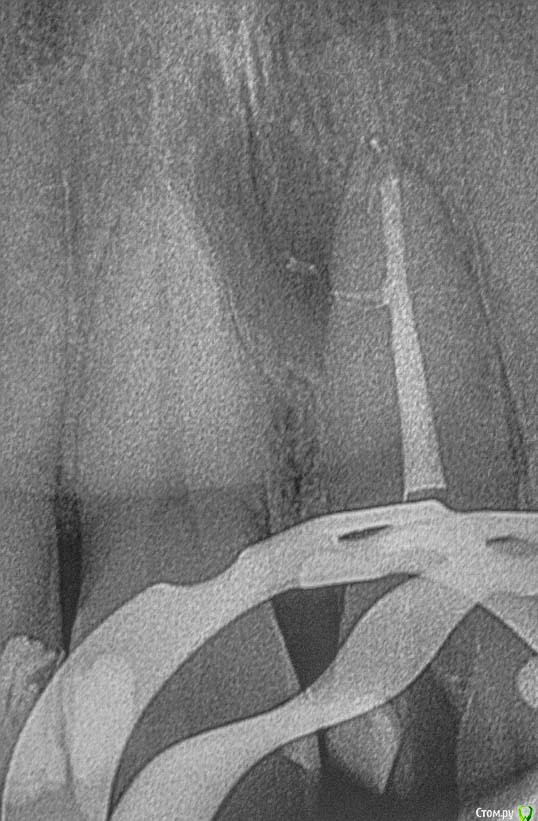

M@estro Опубликовано 9 июля, 2015 Автор Поделиться Опубликовано 9 июля, 2015 Тоже подниму тему. Травму отрицает, жалобы на потемнение. Витальность "-", перкуссия "-" , на рентгене подсказка - есть латераль. Вперёд, мыть ! 60 апекс, гибрид паковка. 1 час с пломбой 7 Ссылка на комментарий